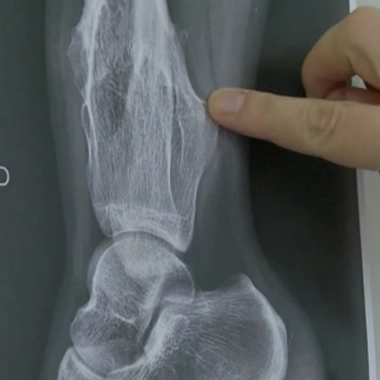

"Concernant la nocivité du lait pour les articulations, il s'agit d'une croyance. Il n'existe aucun lien. Les douleurs ostéo-articulaires sont les douleurs les plus sensibles à l'effet placebo. On est aux alentours de 50%. C'est-à-dire que si un médecin dit quelque chose ou donne un cachet alors qu'il s'agit d'une poudre de perlimpinpin, il a une chance sur deux d'améliorer le patient."